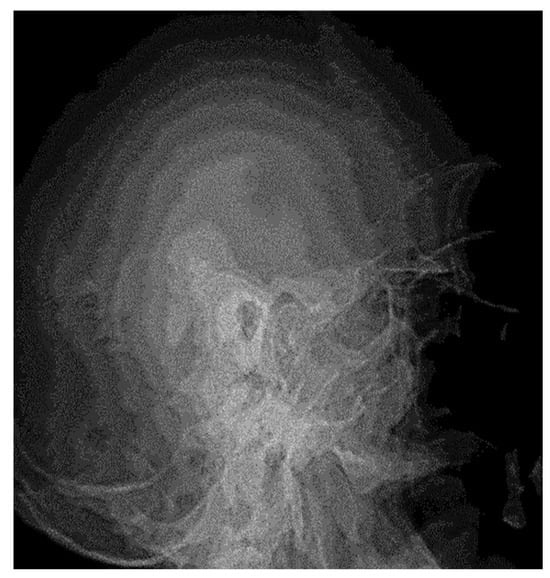

3.1.1. Conventional Radiology